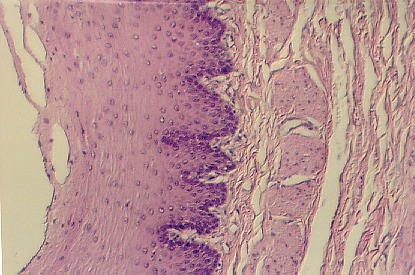

STRATIFIED SQUAMOUS EPITHELIUM

ESOPHAGUS

Stratified squamous epithelium has layers

of scale-like cells. What is the major function of this type of epithelium? The basal

layers of cells are stained dense purple. The apical layers face the esophagus lumen and

sometimes they are slo loughing off. Can you define the layers of this

epithelium?